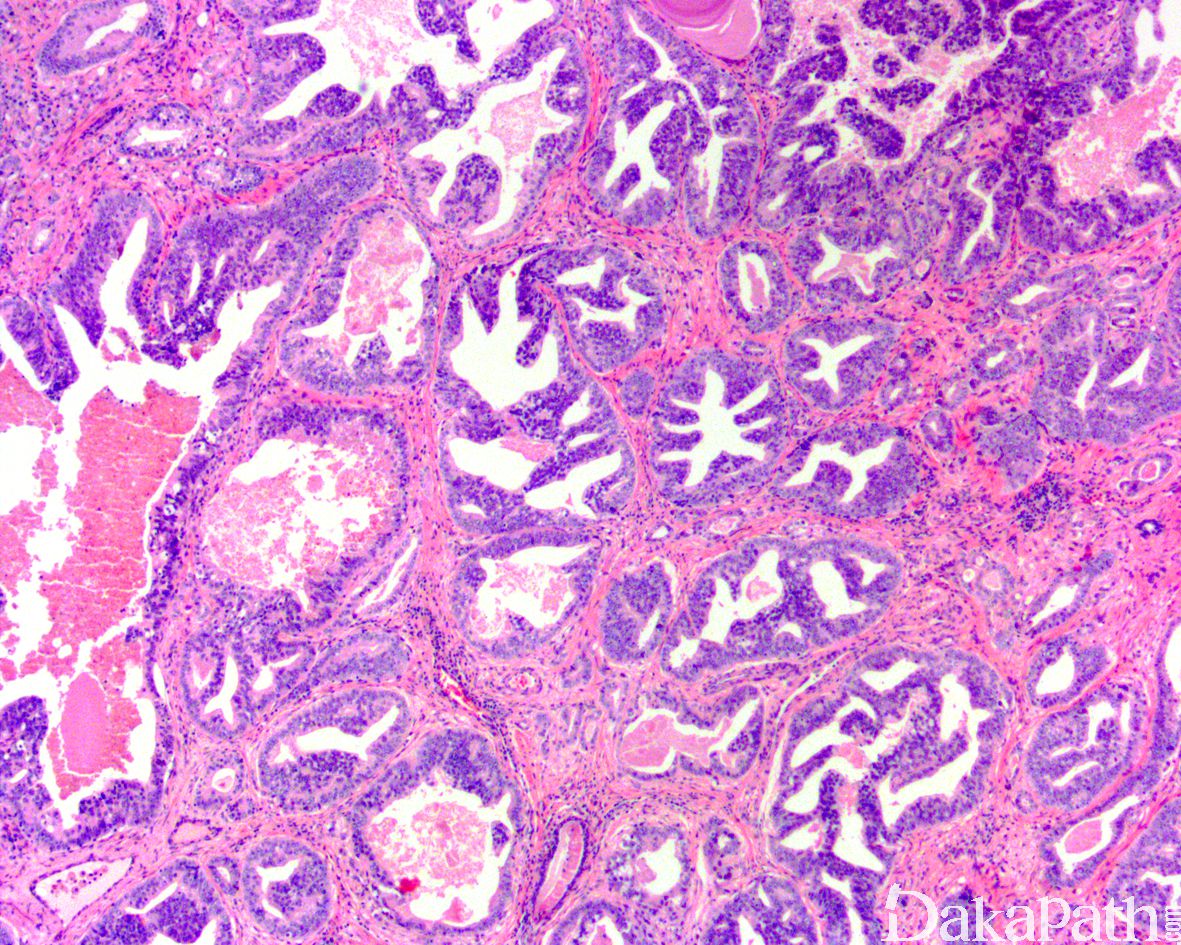

肿瘤性腺体通常排列密集,呈囊性扩张,被覆上皮呈假复层排列,柱状或圆形,腺腔内瘤细胞呈平坦型、微乳头状、簇状或纤细而薄的长乳头状生长(可见纤细的纤维血管轴心)凸入腔内;

PIN 样腺癌的病灶面积通常较小,多数与普通型腺泡性腺癌伴随,伴随的腺泡性腺癌的 Gleason 评分通常为 7 分或 7 分以下;